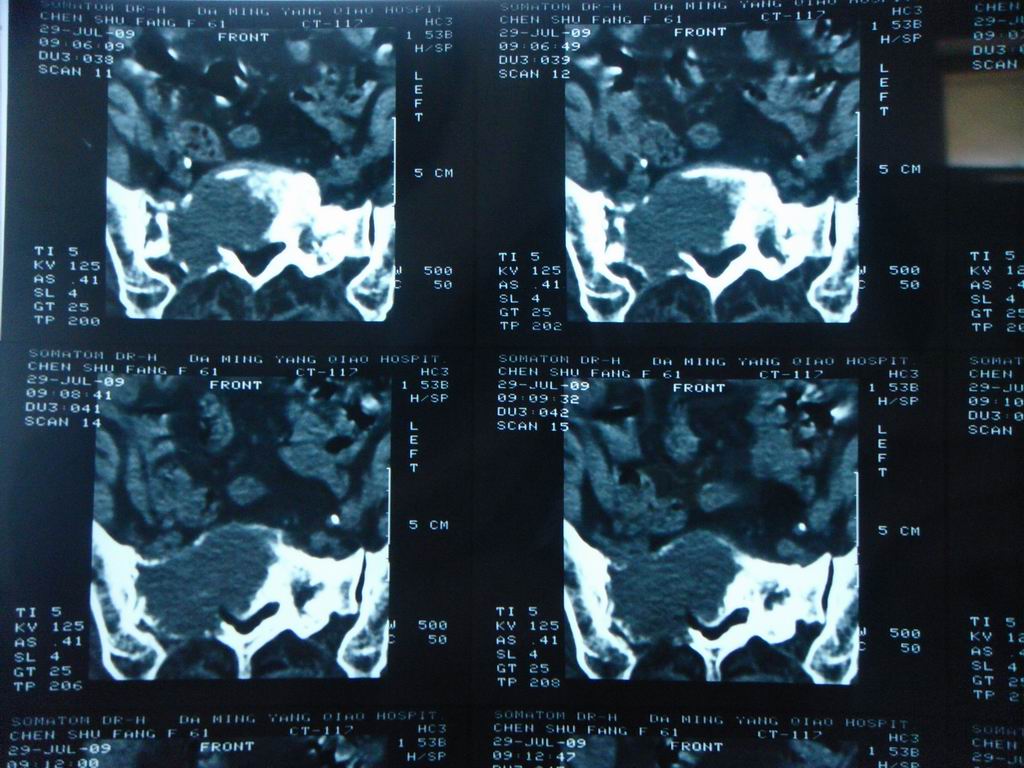

标题: CT21430:女性65岁 乳腺癌术后3年 [打印本页]

标题: CT21430:女性65岁 乳腺癌术后3年

结合病史,考虑骶骨转移瘤,但软组织肿块未突破骨壳,骨巨细胞瘤不能完全排除,骨髓瘤及脊索瘤不考虑。

结合病史,考虑骶骨转移瘤。

结合病史,考虑骶骨转移瘤。其它椎体,如腰5是否有问题呢?

个人感觉骨巨细胞瘤可能性大些。